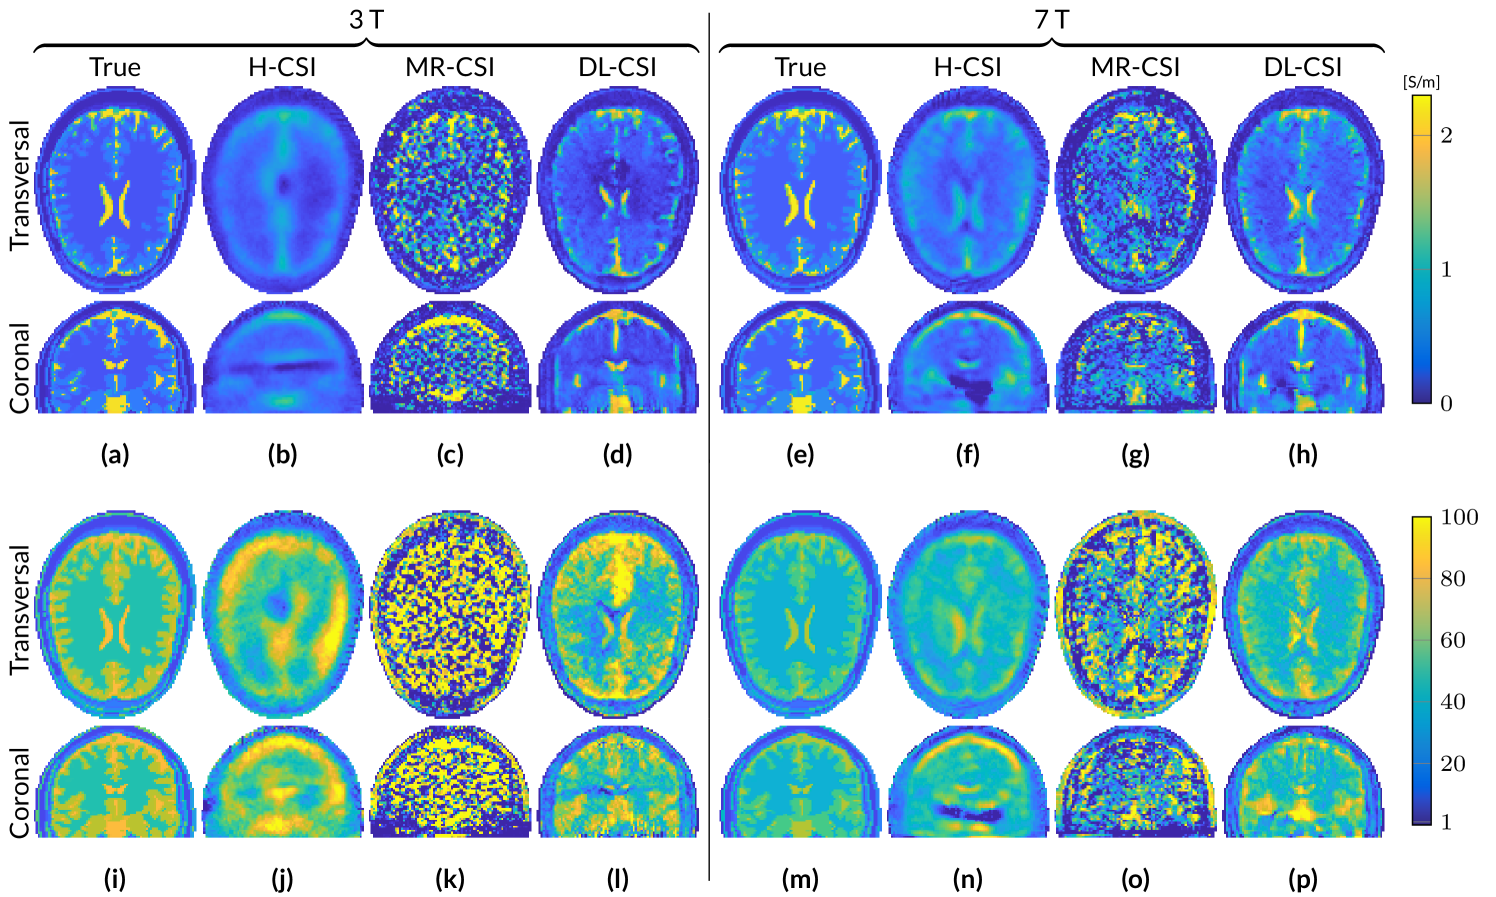

Figure 1: Reconstructed EP maps from different EPT reconstruction approaches for the male head model at 3 T and 7 T based on noiseless B^1+superscriptsubscript^𝐵1\hat{B}_{1}^{+} data. Conductivity (a-h) and permittivity (i-p).

Figure 1 shows EP reconstructions at 3 T and 7 T for noiseless simulated B^1+superscriptsubscript^𝐵1\hat{B}_{1}^{+} data using the standard 3D CSI-EPT (H-CSI) and the two hybrid CSI-EPT approaches (MR-CSI and DL-CSI). All the results are obtained after 500 CSI iterations (taking around 60 minutes on a standard computer for this reconstruction domain size), at which point the mismatch functional has decreased to a value of about 5×1055superscript1055\times 10^{-5}.

At 3 T, H-CSI produces very poor EP maps. The conductivity map shows a smooth reconstruction with underestimations of the high conductivity values. The permittivity map shows less of the underlying tissue structure and the white matter region contains clear overestimations. Furthermore, distorted reconstructions are observed in the center of the object in both EP maps, corresponding to the region with a low electric field strength. For MR-CSI conductivity reconstructions, an improvement is observed especially at the periphery of the head, i.e. away from the low |𝑬^|^𝑬|\hat{\bm{E}}|-field region. However, in the low |𝑬^|^𝑬|\hat{\bm{E}}|-field region (ventricles), conductivity reconstructions are still erroneous. MR-CSI permittivity reconstructions shows severe distortions throughout the brain, reflecting the severe boundary errors of standard MR-EPT reconstructions (see Figure S1). The DL-CSI approach shows better tissue reconstructions of the ventricles compared to H-CSI and MR-CSI. They are clearly visible in both the conductivity and permittivity map. However, even though the reconstructed DL-CSI EP values are close to the ground truth values, small errors arising from the DL-EPT reconstructions used as initialization step (see Figure S1) are visible at the periphery of the head. Note that the DL-CSI reconstructions presented in this figure assumes noiseless data, while DL-EPT reconstructions used as initialization for DL-CSI are available only for noisy data, since the available neural network was trained only on the noisy B^1+superscriptsubscript^𝐵1\hat{B}_{1}^{+} data to better resemble realistic scenarios from MR-measurements.

At 7 T, similar results are observed for H-CSI as at 3 T: a smoothed version for the reconstructed conductivity, and overestimations in the homogeneous WM region for the reconstructed permittivity. Also the low |𝑬^|^𝑬|\hat{\bm{E}}|-field region is clearly visible, which at 7 T is located further down compared to the 3 T case (compare the coronal slices of Figure 1b,j with 1f,n). MR-CSI at 7 T shows boundary artifacts, which are the result of the intrinsic errors of MR-EPT at tissue boundaries. However, compared to its initialization (Figure S1), improvements are observed in the conductivity maps. DL-CSI reconstructions at 7 T (using as initialization DL-EPT reconstructions at 3 T) show higher structure fidelity compared to DL-EPT reconstructions, especially around the ventricles.